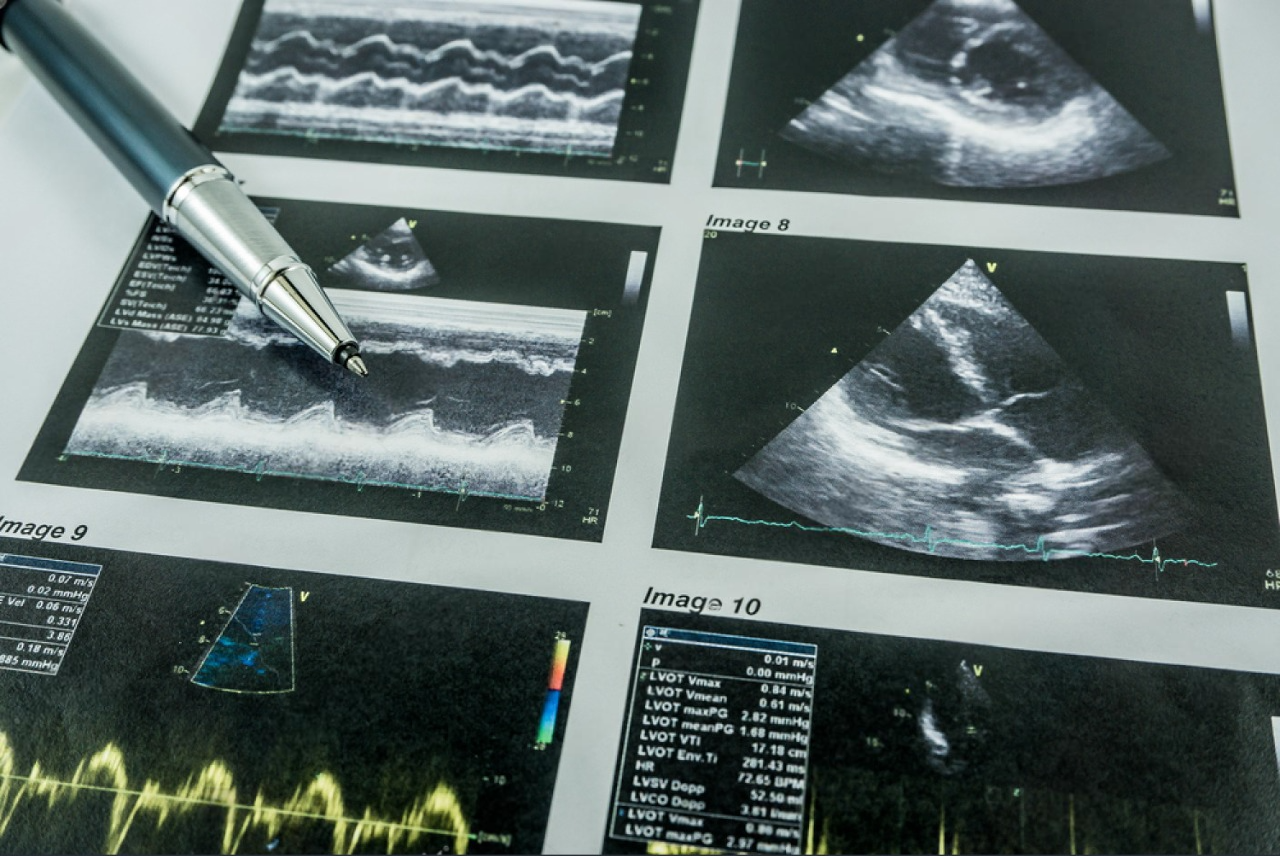

Фокусированная Эхокардиография

В современном медицинском мире ультразвуковая диагностика играет ключевую роль в выявлении жизнеугрожающих патологий. Умение правильно интерпретировать данные может спасти жизни пациентов. Этот курс разработан для специалистов в области медицины, желающих углубить свои знания и практические навыки в оценке сердечно-сосудистой системы. Курс будет интересен как новичкам в качестве "постановки руки", так и активным пользователям прикроватного ультразвука с целью расширения профессиональных компетенций.

• Допплеровское исследование.

11:00 – Лекция: Допплеровское исследование и его применение в эхокардиографии. Оценка диастолической функции ЛЖ, давления в легочной артерии, диагностика аортального стеноза, митрального стеноза. Оценка ударного объема ЛЖ.